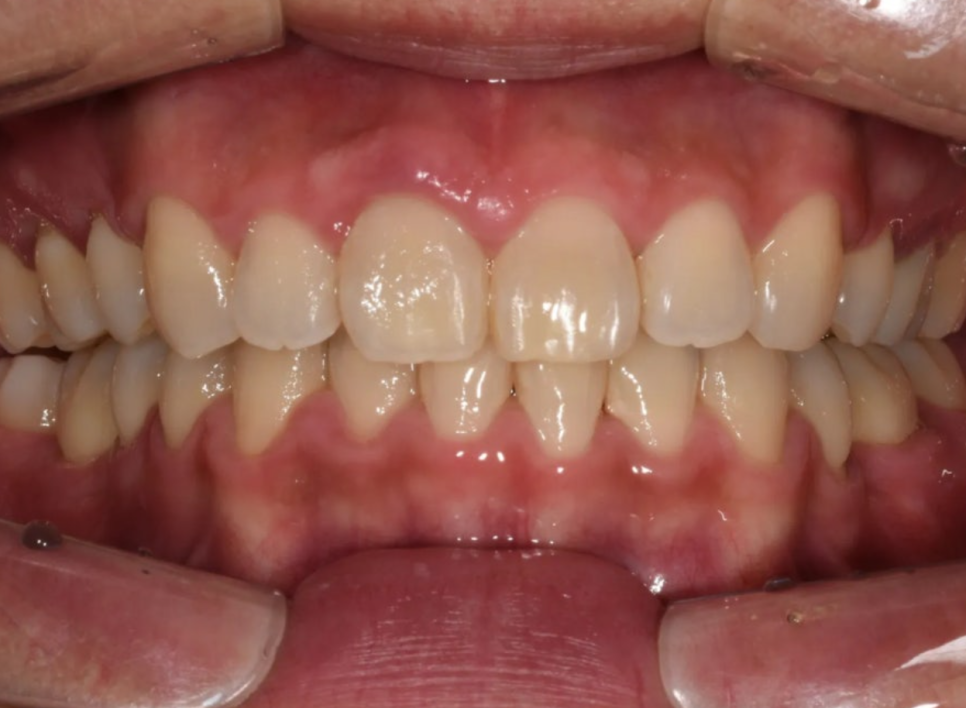

치료 완료 – 돌출입 개선, 정상 교합 형성, 가지런한 치열

드디어 교정 장치를 제거하고 최종 결과를 확인하였습니다.

치열이 정말 가지런하게 배열되었고, 환자분이 가장 원하셨던 돌출입도 예쁘게 개선되었습니다. 옆모습이 크게 달라졌습니다.

무엇보다 중요한 건, 오른쪽 교합이 정상적으로 물리게 되었다는 점이라고 할 수 있습니다. 턱을 왼쪽으로 틀어서 물어야 했던 불편함이 해소됐고, 과개교합도 개선되어 위아래 앞니가 물리는 깊이가 정상 범위로 돌아왔습니다.

편하게 무는 모습이 느껴지십니까?

처음에 돌출입 하나로 오셨지만, 종합적인 진단을 통해 교합(기능) + 심미성 + 장기적 건강 모두를 개선할 수 있었던 케이스였습니다.